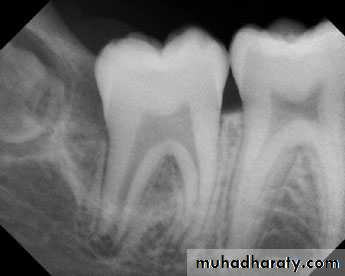

Teeth are composed of pulp (arrow on the secondmolar), enamel (arrow on the first molar), dentin (arrow onthe second premolar), and cementum (usually not visibleradiographically).

Radiographic Anatomy Basics: The Tooth

Radiographic Anatomy Basics